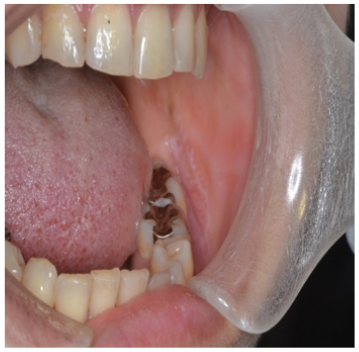

Leukoplakia on left buccal mucosa (Figure 1)

The third molars and the next are filled with metal and adjacent these the white patch and linear were seen on the left oral mucosal area.